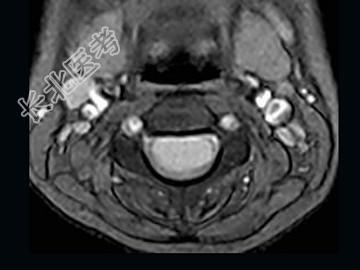

- 单项选择题女,9岁, 颈部疼痛、活动受限2个月,MRI检查如图, 最可能的诊断为 ( )